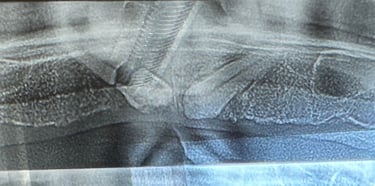

Reabilitare implantara in cazul unor dinti restanti irecuperabili, cu mobilitate severa. Dupa extractia atraumatica a dintilor compromisi, tratamentul continua cu inserarea implanturilor dentare. In prealabil, in urma cu 6 luni s-a realizat aditie osoasa prin sinus lift extern la nivelul cadranului II, tehnica chirurgicala care ne-a permis inserarea implanturile posterioare.